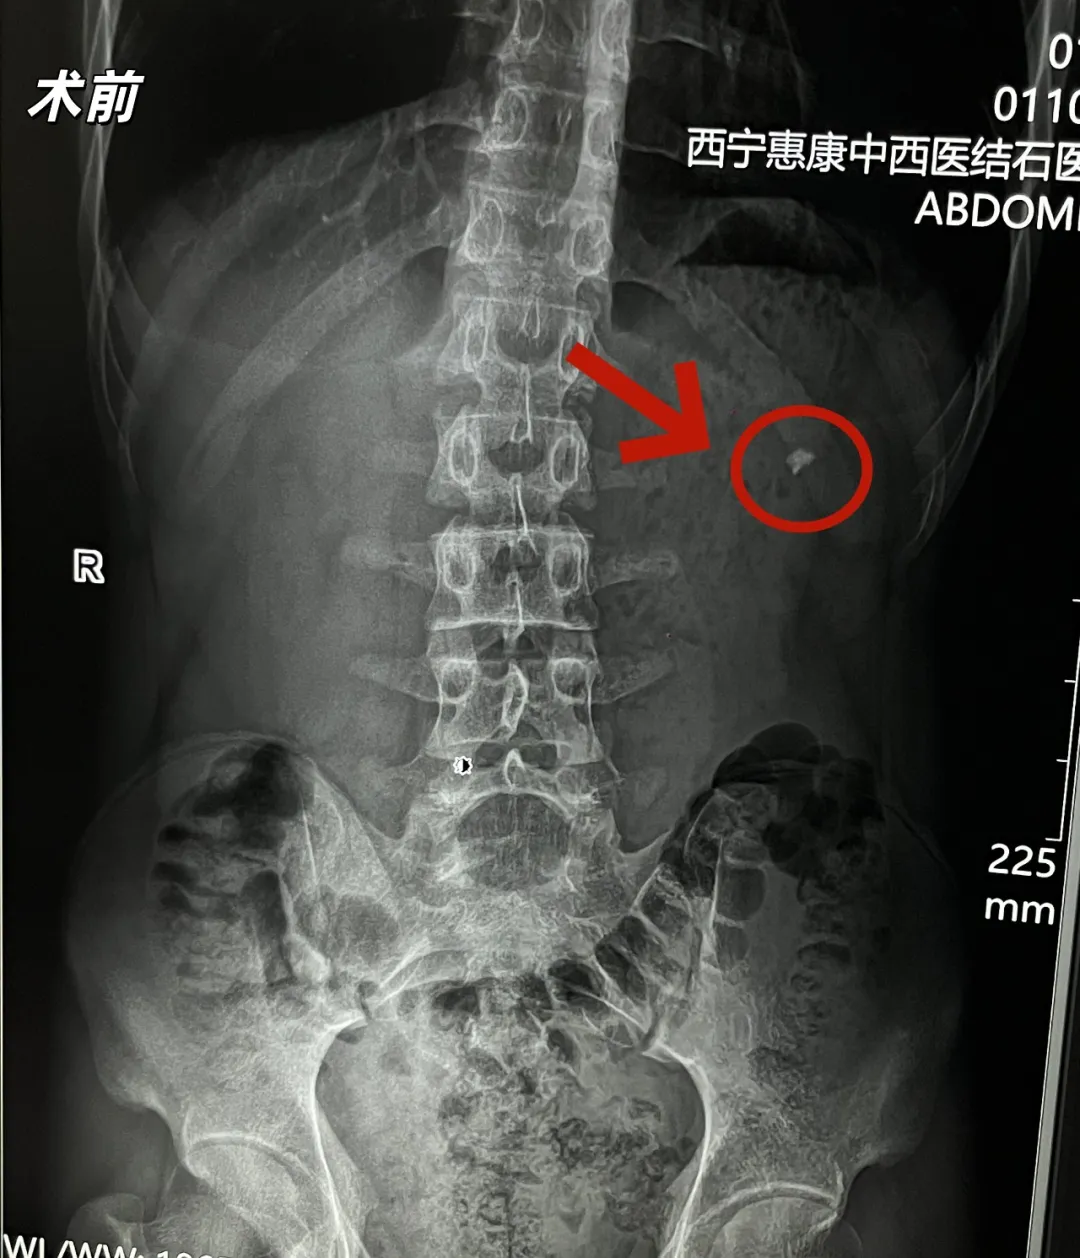

近日,我院外科收治了一位病情复杂的15岁男性患者。该患者因无明显诱因间断出现左侧腰部酸胀不适来院就诊,经详细检查后,被明确诊断为:左侧肾结石伴有积水和感染、左侧输尿管狭窄。

面对这一复杂的病情,我院外科团队高度重视。考虑到患者年龄小、结石不大,且合并肾孟输尿管连接部狭窄,科室最初与家属沟通为患者行肾盂输尿管成形术+肾盏内结石取石术,以期从根本上解决输尿管狭窄的问题。但患者家属因孩子小,对于肾孟输尿管成形手术表达了不同意见,且要求治疗肾中上盏结石。

尊重患者家属的意愿,我院外科及手麻科团队随即重新进行严谨的术前评估。患者输尿管存在狭窄段,这使得常规的输尿管软镜和硬镜均无法顺利通过并到达结石部位,取石路径受阻。在必须处理结石的情况下,团队经过充分讨论,将方案聚焦于经皮肾镜碎石取石术。这是临床处理此类复杂肾结石的常用技术之一。

然而,手术的挑战接踵而至。术中,在B超引导下进行穿刺定位时,团队发现患者的结石位于肾的中上盏,目标穿刺点位置偏高。若按常规思路直接穿刺高位目标点进行碎石,存在损伤胸膜的风险,对年仅15岁的患者而言,手术安全性必须放在首位。